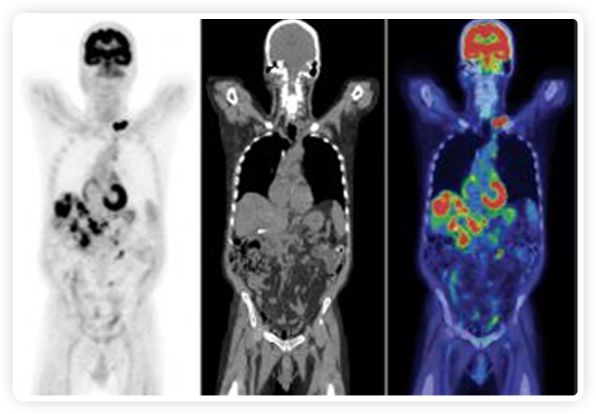

提起放療設備的引導系統(tǒng),大家通常會想到結構性成像的CT或核磁。但你有沒有想過用功能性成像來引導放療呢?美國的一家醫(yī)療器械公司從2011年就致力于研究開發(fā)用PET提供生物學指導放射治療的設備BgRT。BgRT能實時利用癌癥的生物學特征作為信號指導治療全身腫瘤。

到目前為止,放射腫瘤學中(使用的圖像主要是結構性的,而PET圖像可以提供生物學信息。通過使用注射示蹤劑,例如18-FDG,PET可以描繪腫瘤的代謝活性,使其“點亮”。(FDG是用于可視化癌癥代謝的最廣泛使用的示蹤劑。與正常組織相比,腫瘤細胞保留更高水平的FDG。)不同的PET示蹤劑可以識別腫瘤的不同生物學特征,例如特定生物標志物抗原(例如,PSMA)或甚至探測免疫系統(tǒng)本身(例如,PDL1表達或活化的T細胞)。

PET+放療共同治療

RefleXion將PET成像與立體定向放射治療相結合。在注射示蹤劑后,RefleXion的技術基于示蹤劑信號實時地在一個或多個目標上引導治療性X射線。使用這種專有方法,RefleXion的平臺有可能比現(xiàn)有系統(tǒng)向癌癥病變提供更高劑量的輻射,并改善周圍健康組織的保護。

為了避免PET長圖像采集時間,RefleXion開發(fā)了一項專利技術使用重合的PET光子對來指導放射治療束,因為實時檢測發(fā)射的光子,為生物指導提供了一種時間有效的方法。